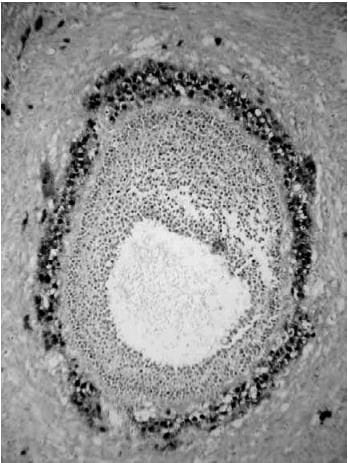

The histological appearances of the corpus luteum, showing

(a) an active corpus luteum

(b) regression of the corpus luteum with histiocyte infiltration